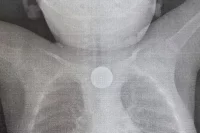

В приёмно-диагностическое отделение ДРКБ привезли семилетнего мальчика, который получил травму при катании на «ватрушке» с необорудованного склона. У него диагностировали закрытый перелом бедренной кости со смещением. Врачи отмечают, что в оборудованном безопасном месте для катания ребёнок не пострадал бы так серьёзно.

«В экстренном порядке мальчика прооперировали, и, несмотря на сложность травмы, вмешательство завершилось успешно, — рассказали в пресс-службе медучреждения. — Ребёнок получил необходимое лечение в отделении травматологии и ортопедии. В среднем на сращение подобного перелома нужно 5-6 недель, но на реабилитацию уйдёт несколько месяцев. Всё зависит от особенностей организма и соблюдения рекомендаций врача».